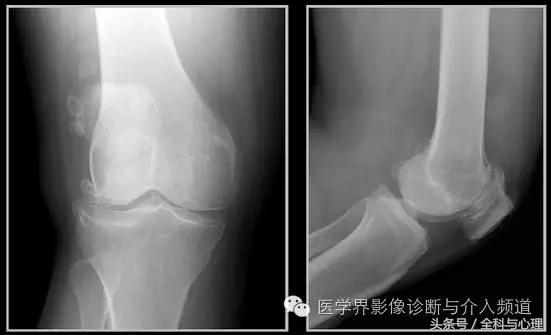

半月板钙化

耻骨联合软骨钙化